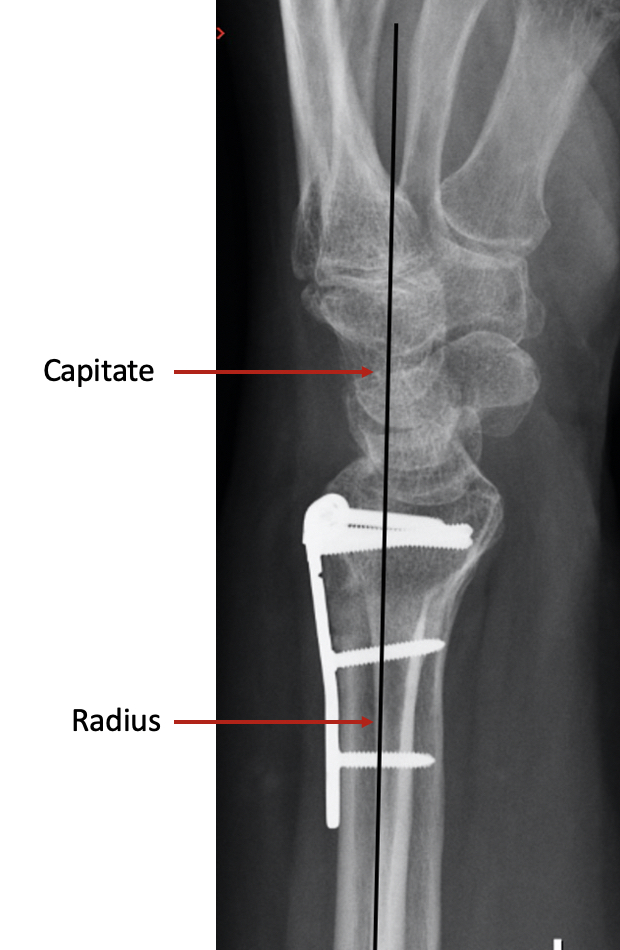

The surgery involves making an incision over the area of the malunion, and using a fine saw, the bone is divided. The bones are then repositioned in a more normal alignment and usually a small plate is used to fix the bone in its new position. On a normal side view xray (lateral view), if you draw a line up the middle of the radius bone, then this line should continue through the middle of the capitate bone. In a malunion, the continuing line does not pass through the middle of the capitate. The aim of surgery is primarily to restore this line.

Unlike an acute fracture, the surrounding soft tissues undergo minimal damage and therefore once the bone has healed, the wrist usually recovers quickly, with return of function within 3 months, rather than the slow process seen after a fracture. Often, a bone graft will be needed to fill the gap which appears in the bone when the position is corrected. Bone graft is the name given when a small piece of bone is taken from another area, usually the pelvis where it is not missed much, and put in a new position to supplement the existing bone.

Unfortunately, one of the significant risks of this type of surgery is failure to maintain the new position of the bone – ie recurrent malunion, but most patients report high satisfaction levels 1 year after corrective surgery.